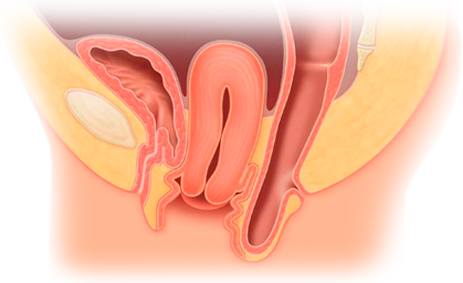

Tengo como compromiso mejorar la salud de nuestra comunidad y promover la prevención de patologías que afectan al aparato urinario, glándulas suprarrenales y retroperitoneo de ambos sexos, y el aparato reproductor masculino.

El Dr. Alejandro Palmeros Rodríguez es un médico especialista en urología comprometido con el bienestar de sus pacientes. Mediante su conocimiento y el uso de tecnología puede lograr la recuperación de distintos padecimientos y lograr una vida sana.